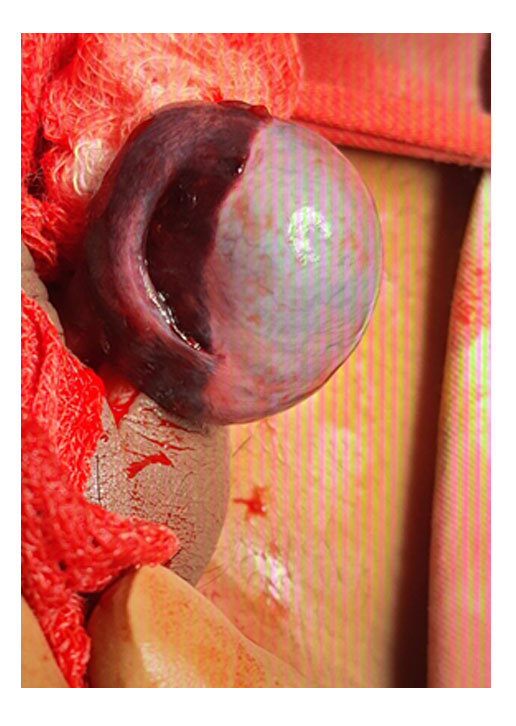

Undescended testis